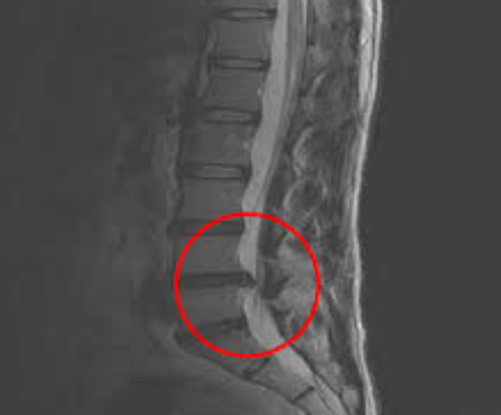

협착증은 척추관이 좁아져서 신경이 눌리는 질환입니다. 나이가 들수록 척추 주변 뼈와 인대가 두꺼워지고, 디스크도 조금씩 튀어나오면서

신경이 눌리는 공간이 점점 줄어들게 됩니다.

즉, 디스크보다 더 나이와 관련된 퇴행성 질환으로 보는 것이 맞습니다.